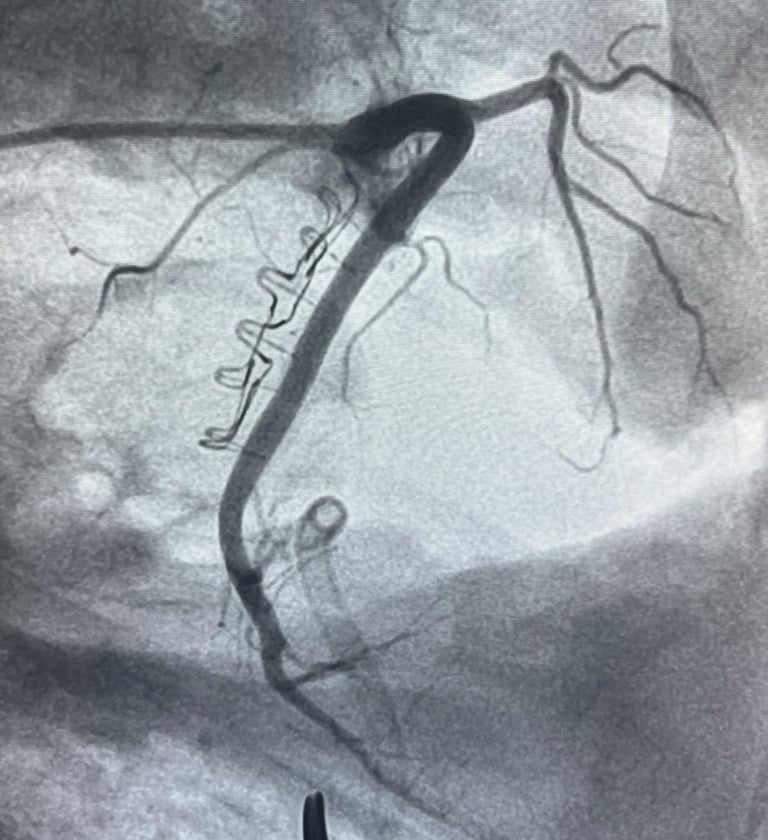

Cinch Annuloplasty Device

Cinch Medical is developing catether-based solutions to functional tricuspid regurgitation.

The Cinch Annulizer will provide quick and easy first line treatment for TR providing a standardized all-comers approach to annuloplasty.

Annuloplasty simplified